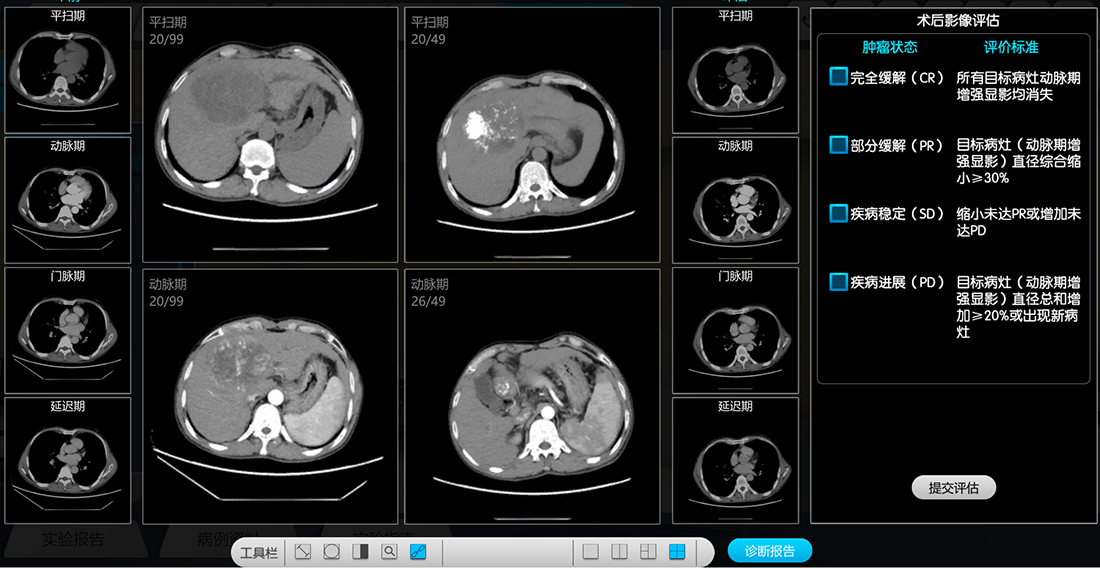

恒点的虚拟仿真系统构建了覆盖癌症诊断全流程的沉浸式学习环境,实现真实临床场景的“无风险复刻”。

通过虚拟仿真,学生可以在安全环境中反复试错,培养临床决策能力。操作失误不会伤害真实患者,这种心理安全感反而提升了学习效率。恒点的虚拟仿真资源管理平台让教学不再受地域限制,让各地学生都能获得与顶尖医学院同质的教学资源。

XR数字融合工作站的虚拟仿真教学系统能够精准呈现肿瘤形态特征,内置数据涵盖完整临床病例,支持多角度观察实操,让癌症诊断沉浸化和智能化。